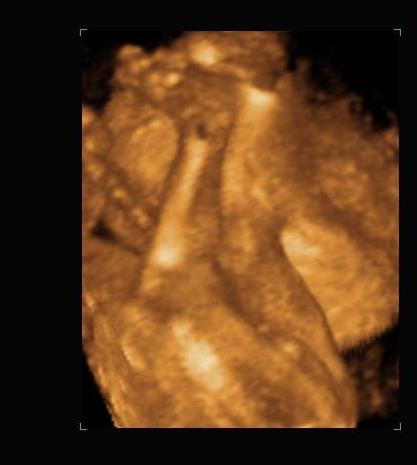

rólunk:

megvolt a 4D a Kárpát utcában, babát rendben találta az uh-s néni.

sajna nagyon elbújt a baba, így nem sok képet tudott csinálni róla, de kettőt azért felteszek.

arcocska

Kép

a kisfiús szülők táborát erősítjük. :-)